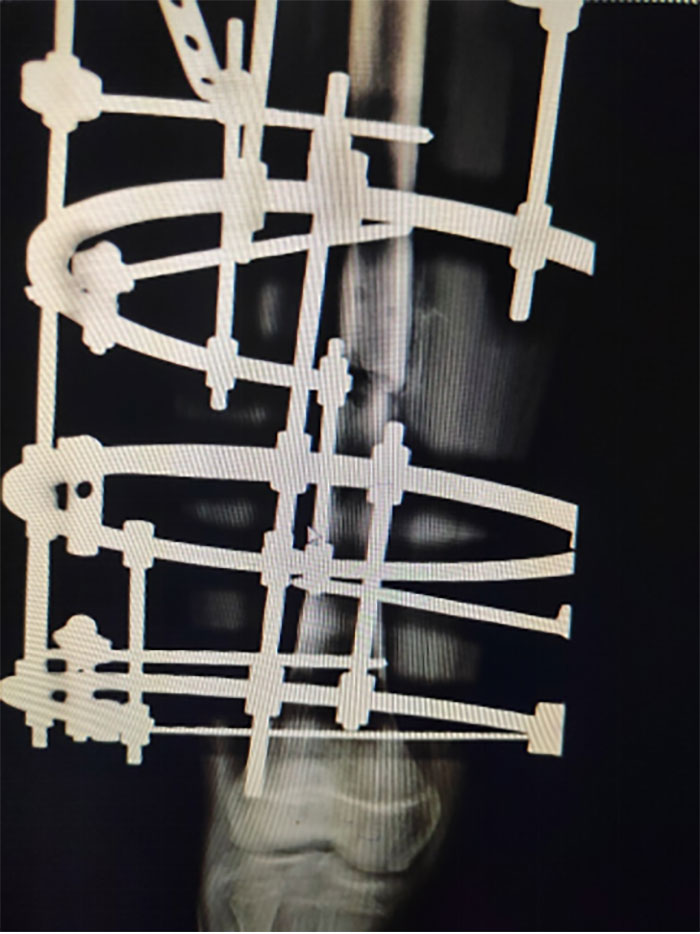

對(duì)于患者來說,時(shí)間就是生命。為了在治療燙傷的同時(shí)不耽誤患者下肢骨折的治療,經(jīng)過多學(xué)科會(huì)診討論后,金馳主任決定采用基于Ilizarov技術(shù)的洞孔環(huán)式外固定架進(jìn)行股骨骨折的復(fù)位和外固定術(shù),使患者燙傷和骨折同時(shí)進(jìn)行恢復(fù),以便于早期拄拐下床活動(dòng),降低患者的痛苦和臥床時(shí)間。

在麻醉科的配合下,手術(shù)如期進(jìn)行,術(shù)中創(chuàng)傷骨一科(骨七科)團(tuán)隊(duì)盡最大可能減少對(duì)患者燙傷皮膚的干擾,同時(shí)本著微創(chuàng)治療理念,對(duì)右側(cè)股骨干骨折實(shí)現(xiàn)了小切口復(fù)位+IEF外固定架的固定,手術(shù)經(jīng)過2個(gè)小時(shí)后順利完成,既保護(hù)了大面積的燙傷皮膚,又實(shí)現(xiàn)了骨折滿意復(fù)位、可靠固定的目的。